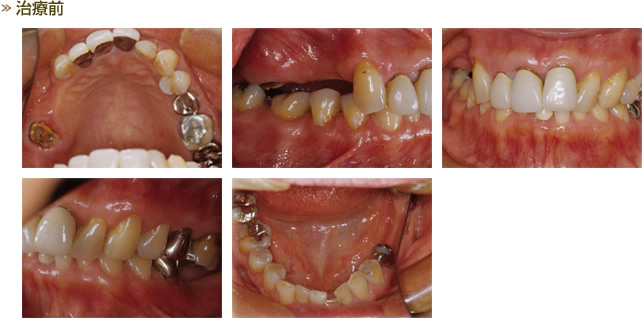

CASE4 歯周外科(歯冠長延長術)

治療前・治療後の写真です。 歯周外科(歯冠長延長術)を全顎的に行い、レジン前装鋳造冠にて修復しました。